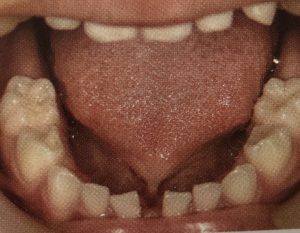

舌小帯への対応

舌小帯の短縮や付着異常があると、舌の動きが抑制され、哺乳、咀嚼、エンゲ、発音時に舌の運動機能障害を引き起こします。舌の挙上が難しいため、舌の前方突出と低位舌の原因となり、エンゲ時に下顎前歯が前方に押され歯並びにも影響があります。

新生児期に授乳困難な場合には、出産後すぐに舌小帯手術を行うかどうかを判断するために、機能の検査も兼ねて舌の基礎的な運動機能を確認します。この審査は舌を前に出す、舌を左右に動かす、舌と口蓋でポンと音を鳴らすことで、幼児期の子供でも行えます。中にはこの運動を行うことで、舌小帯の伸展が見られ、手術が必要なくなる場合があります。

この時、舌に著しい運動障害が確認される場合は、舌小帯切除術を行った方が良いです。また舌小帯切除術を必要とする場合でも、この審査を行うことが術前の舌挙上トレーニングになり、舌小帯の伸展と術後の瘢痕化防止の効果が期待できます。